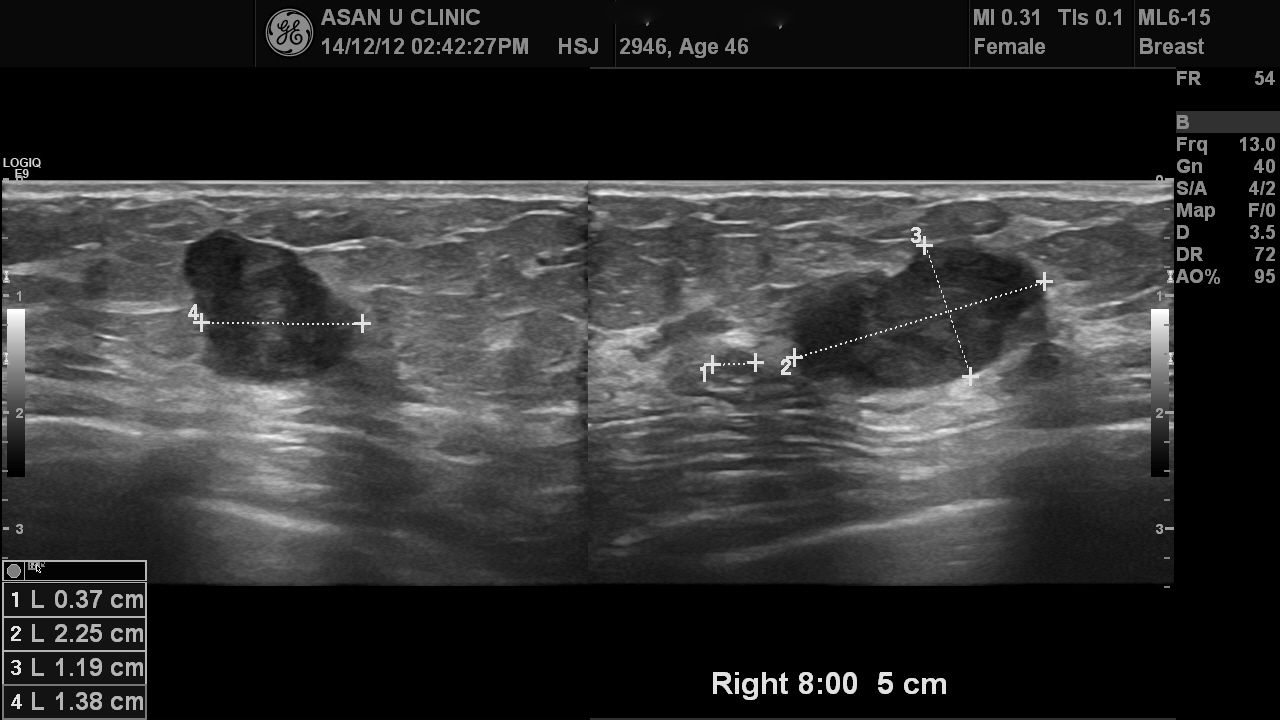

이삼일전부터 만져지는 몽우리가 오른쪽 유방에 있어서 오신 만 46세 여성분입니다.

2.25cm의 혹이 하외측에 있었고 조직검사로 침윤성 유관암으로 진단되었습니다.

유륜쪽으로는 거리가 있어서 부분절제로 수술이 가능할 것으로 생각되나

0.5cm전후의 작은 혹들이 주변에 떨어져 있어

유방 MRI를 통해 반드시 없애야 할 혹들을 더 점검해야 합니다.